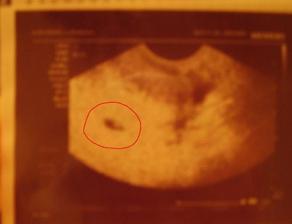

Ahojteee, tak som uz tu, na svet som prisla v piatok 28.11.2008 o 0:40, rychlo, bez problemov a s mierami 3350g a 50cm. Som vlasata nadherna, a volam sa